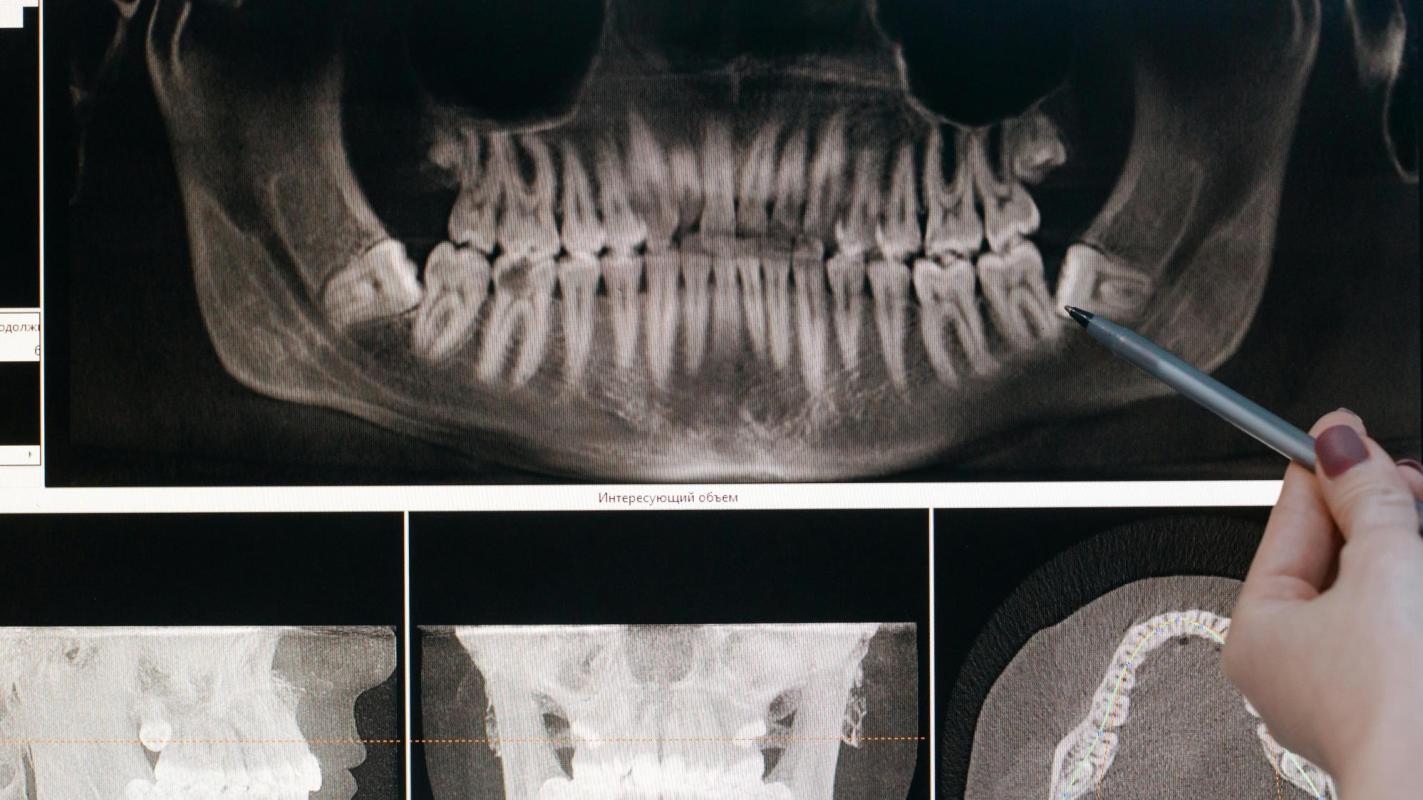

Las bacterias utilizan los azúcares de la dieta y forman ácidos. Con el tiempo, este proceso puede ir debilitando las partes duras del diente. Afecta, por ejemplo, al esmalte, ya que sustrae minerales esenciales como el calcio y el fosfato, que son los encargados de mantenerlo resistente y fuerte. A esto se le llama desmineralización.

Sin embargo, en el proceso continuo de desmineralización y remineralización, pueden aparecer manchas blancas opacas en la superficie del diente que está pegada a la encía. Estas manchas representan el primer signo clínico de caries dental (la caries dental no siempre comienza como un “hueco”).

La coloración se debe a que la pérdida de minerales altera la forma en que la luz se refleja en el diente, razón por la que se aprecian estas zonas blancas y opacas. Se podría decir que las manchas blancas son las pistas e indicios con los que el diente avisa. Este mensaje nos advierte que los ácidos están ganado terreno y han comenzado a debilitar su estructura.

Se dice que una lesión de caries está activa cuando continua progresando, ya que las bacterias siguen produciendo ácidos que atacan el esmalte y la dentina. Es como si el diente estuviera atrapado en una lluvia de ácidos, sin refugio para sanar. Por otra parte, la lesión de caries inactiva es la que no ha avanzado. Aunque el tejido dental está afectado, ya no hay actividad bacteriana ni pérdida de minerales.

Aquí comienza el lado menos conocido de las caries inactivas: su avance se ha frenado pero siguen siendo testigos de un pasado de desmineralización y requieren vigilancia.